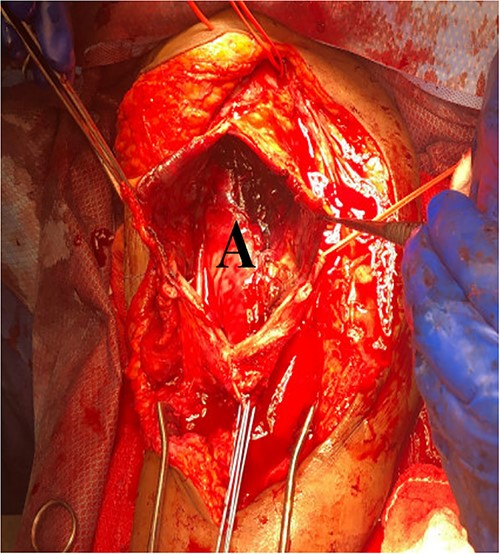

She then re-presented 2 months later with gradually increasing right upper extremity edema with a palpable thrill in the arteriovenous fistula. Duplex identified a large hematoma with patency of the fistula (Fig. 2). A tunneled dialysis catheter was placed to allow the swelling and hematoma to resolve. After medical optimization, the patient consented for operative intervention with the intention to evacuate the hematoma. There was noted to instead be a 20 × 35 cm PSA of the brachial artery (Fig. 3). The median nerve was identified and preserved. After proximal and distal control, the patient was heparinized, and the brachial artery PSA was decompressed with evacuation of large mural thrombi (Fig. 4). This artery segment was resected, and patch angioplasty was performed (Fig. 5). The fistula was ligated, and the distal remnant was preserved. Radial and ulnar pulses were palpable. The patient recovered well postoperatively.